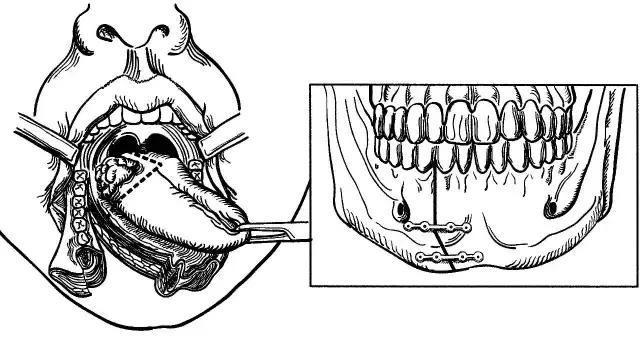

下颌骨分段切除术

下颌骨切除术

口腔癌手术路径图